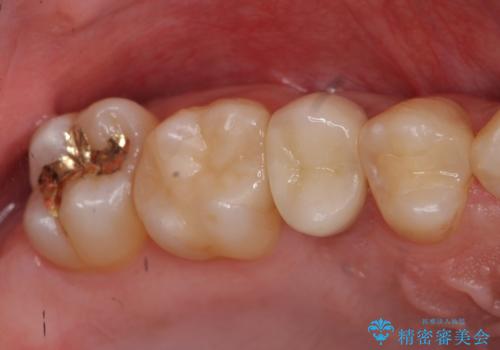

歯の健康な部分を矯正治療で引っ張り出してから、虫歯治療を行なっています。

- 32万円(右上5:ジルコニアクラウン(スペシャル)10万円、仮歯 1万円、エクストリュージョン:10万円、歯周外科治療:エクストリュージョン費用に含む 根管治療:9万円 ファイバーコア:2万円)費用は治療当時の料金となります

終了時

保険治療の範囲ですと予後が期待できません。自費治療では、エクストリュージョンなど選択肢が広がり、しっかりその歯を悪くならない状態に持っていくことが可能です。